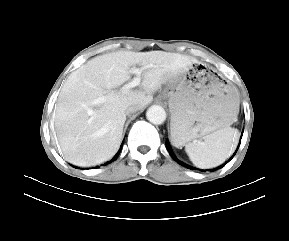

标题: CT19533:病变来源于哪?

患者,男,发现上腹部包块两月余。

病变位于肝胃间隙,实际就是位于小网膜囊(左肝下后间隙),呈轻度不均匀性强化,腹腔内及腹膜后见多发肿大淋巴结。所以我考虑肝胃间隙恶性胃肠间质瘤并淋巴结转移。

病灶与胰腺分界不清,来源于胰腺?

强化后病变与胃壁分界清楚,并且血供不是来源胃壁血管。考虑胰腺颈体癌并腹腔腹膜后淋巴结转移。